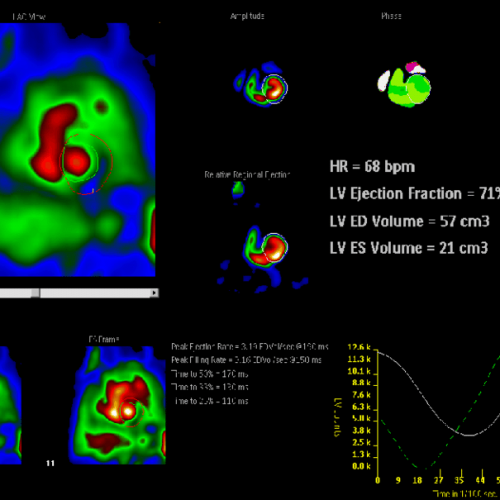

VENTRICULOGRAFÍA ISOTÓPICA (FEVI)

Valoración de la función ventricular en pacientes con tratamiento con quimioterapia o con patología cardíaca.